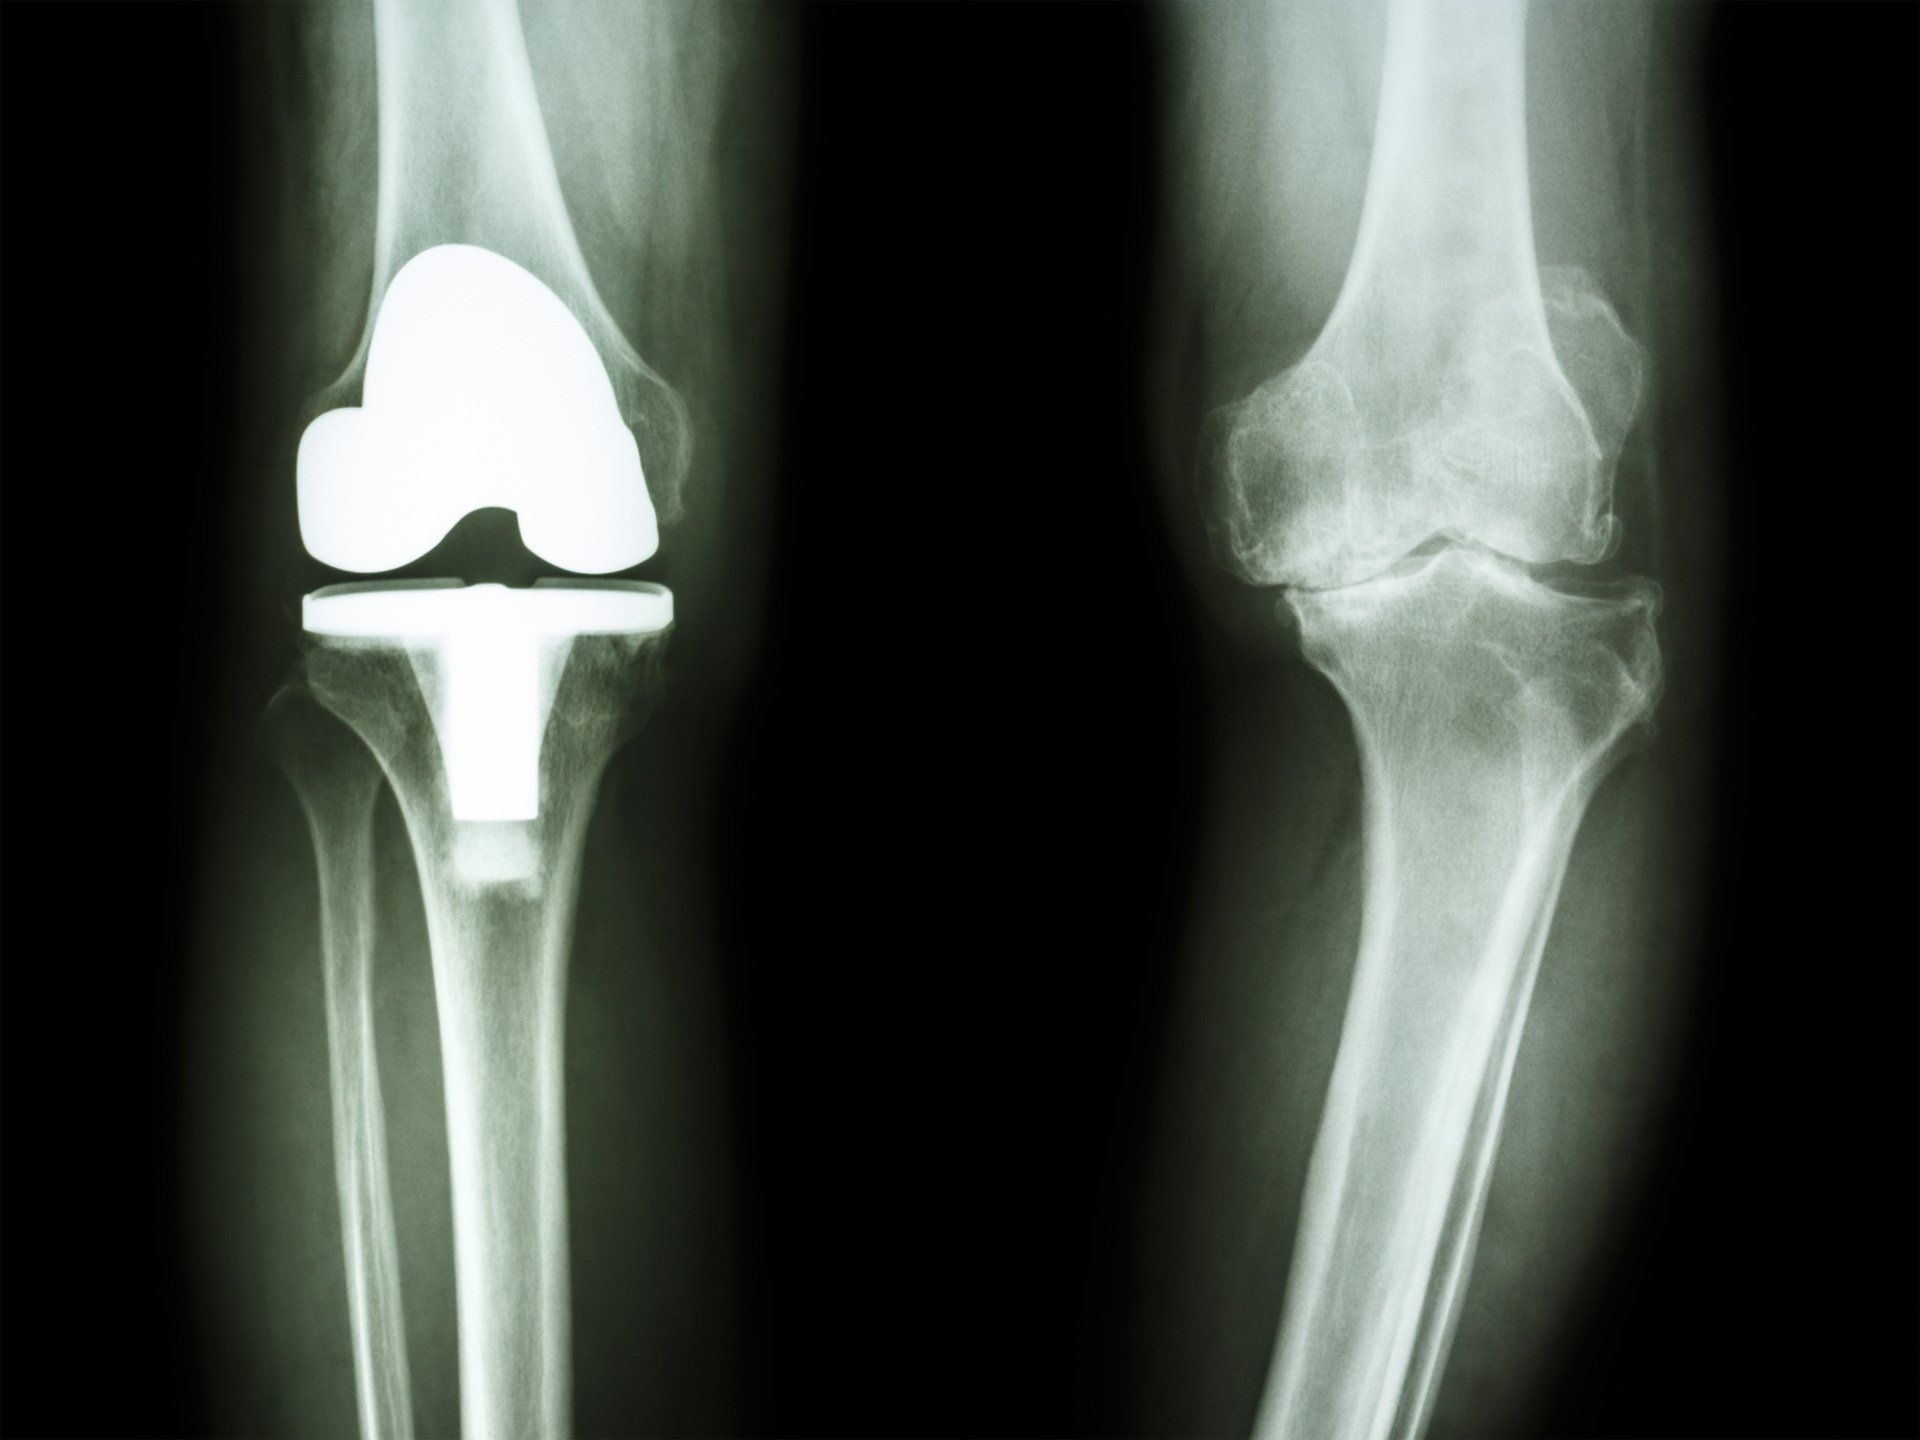

- Ολική αρθροπλαστική γόνατος:

- Κατάλληλο όταν υπάρχει:

- Γενικευμένη συμπτωματική αρθρίτιδα στο γόνατο

- Αποτυχία μη χειρουργικών θεραπευτικών επιλογών

- Περιλαμβάνει την αντικατάσταση της φθαρμένης επιφάνειας της άρθρωσης του γόνατος με μέταλλο πάνω και κάτω, και την τοποθέτηση πλαστικού ανάμεσα